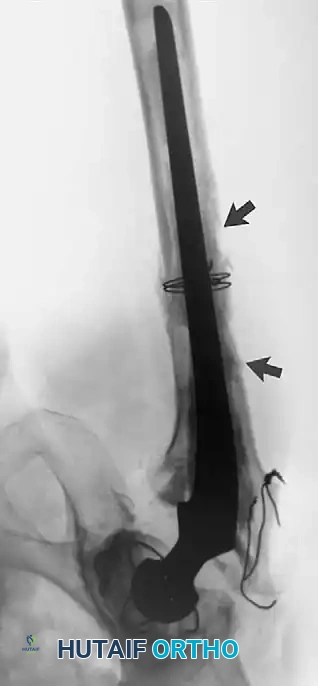

Associated Surgical & Radiographic Imaging